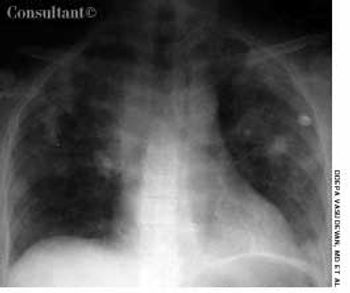

Progressive DyspneaByDeepa Vasudevan, MD,Trevor R. Allison, MDSeptember 14th 2005A 37-year-old woman presented with progressive dyspnea of 2 weeks' duration, a low-grade fever, and night sweats. She had been a healthy marathon runner until her exercise tolerance recently declined.